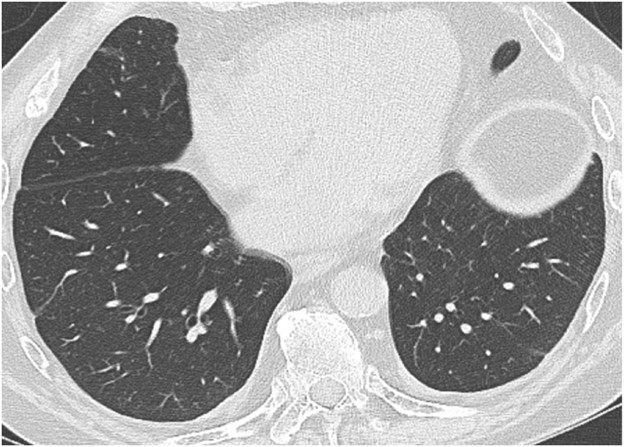

Infection of the lung parenchyma and airways is exceedingly common after lung transplant due to immunosuppression and decreased mucociliary clearance in the airways after transplant. Infection can occur anytime after transplant, including the early postoperative period. Patients are vulnerable to bacterial pneumonia as well as viral and fungal pneumonias not commonly encountered in immunocompetent patients. Common pathogens include Pseudomonas organisms, Staphylococcus aureus, cytomegalovirus, Epstein-Barr virus, herpes simplex virus, Aspergillus organisms, and Candida organisms [2].

The clinical and imaging manifestations of pneumonia in transplant recipients are similar to those of nontransplant patients. Lung transplant recipients who present with dyspnea, cough, or fever are evaluated for pneumonia. Imaging findings of pneumonia include consolidation, ground-glass opacities, septal-line thickening, and pulmonary nodules. Pulmonary nodules can be single or multiple; they may be solid or ground-glass in attenuation. Cavitary nodules and nodules with ground-glass halos can occur, especially in patients with fungal pneumonia. Imaging studies should be scrutinized for complications of infection such as pulmonary abscess and bronchopleural fistula. Patients may also have reactive pleural effusions or reactive mediastinal or hilar lymphadenopathy. Treatment is the same as in nontransplant patients and consists of antibiotics, antivirals, or antifungals depending on the causative pathogen. Figure 4 shows three different lung transplant recipients with pneumonia.